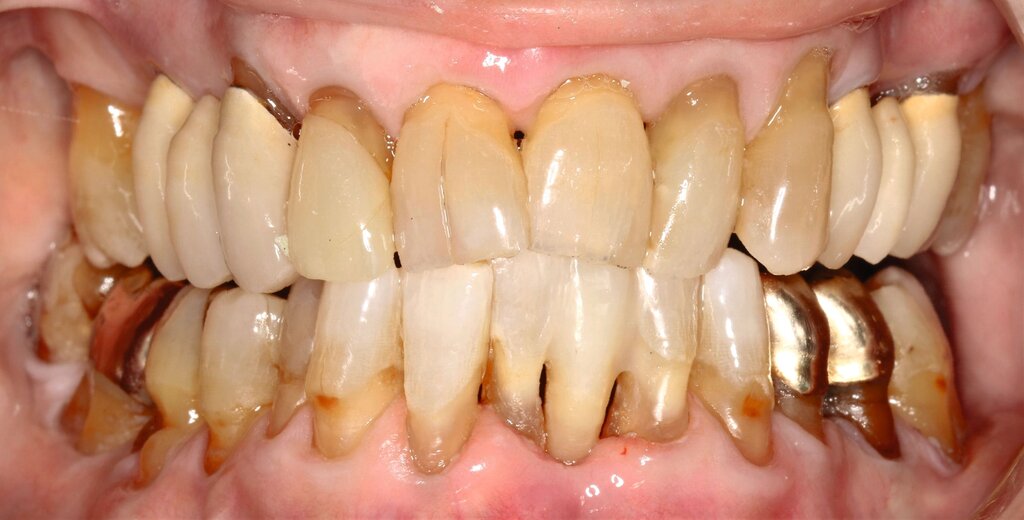

Obwohl die unterstützende Parodontitistherapie (UPT) vier Jahre unterbrochen war, konnte bis auf einen Grad III gelockerten Zahn 31 und eine Grad I–II gelockerte, restliche Unterkieferfrontbezahnung ein gut erhaltenes Gebiss festgestellt werden. Dies ist auch darauf zurückzuführen, dass die Patientin – trotz ihres fortgeschrittenen Alters – die häusliche Mundhygiene stets sehr gründlich betrieb, wie auch aus früheren Akteneinträgen ersichtlich wurde (Abbildung 4).

Da die Patientin bereits seit längerer Zeit Interdentalbürstchen verwendete, war das Anwendungs-Training in diesem Fall weniger komplex. Die Verwendung von Interdentalbürstchen und die Teilnahme an der Nachsorge sind in solch einem Fall grundsätzlich jedoch unerlässlich zur Sicherung des Erfolgs. Empfohlen wurde der Patientin aufgrund multipler freiliegender Zahnhälse sowohl oral/vestibulär als auch approximal (Abbildungen 13 und 14) zusätzlich eine Zahnpaste mit einem höheren Fluoridgehalt (Medelmex Duraphat Fluorid 5 mg/g Zahnpasta, CP Gaba).